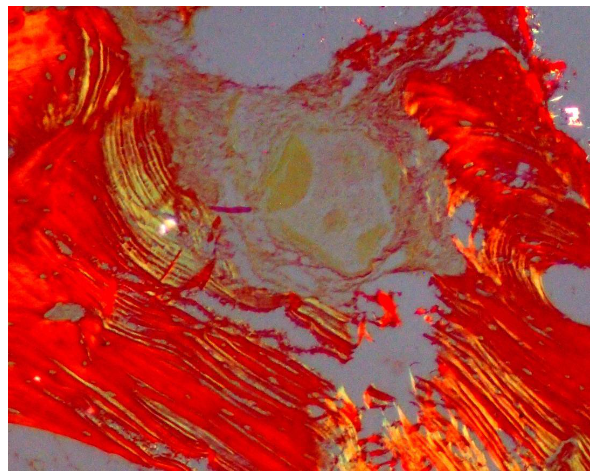

Histological Analysis

Biopsies were fixed in 10% formalin, decalcified with 0.5M EDTA, and sectioned. Hematoxylin and eosin (HE), Van Geison, Mason trichrome and Picrosirius Red were used. Microscopic analysis revealed remnants of dentin particles integrated with new lamellar bone. Plump osteoblasts, entrapped osteocytes, and fibrovascular stroma with minimal chronic inflammation were evident, confirming osteoconductive and osteoinductive potential. Mature bone trabeculae along with residual graft material were confirmed with various special stains.